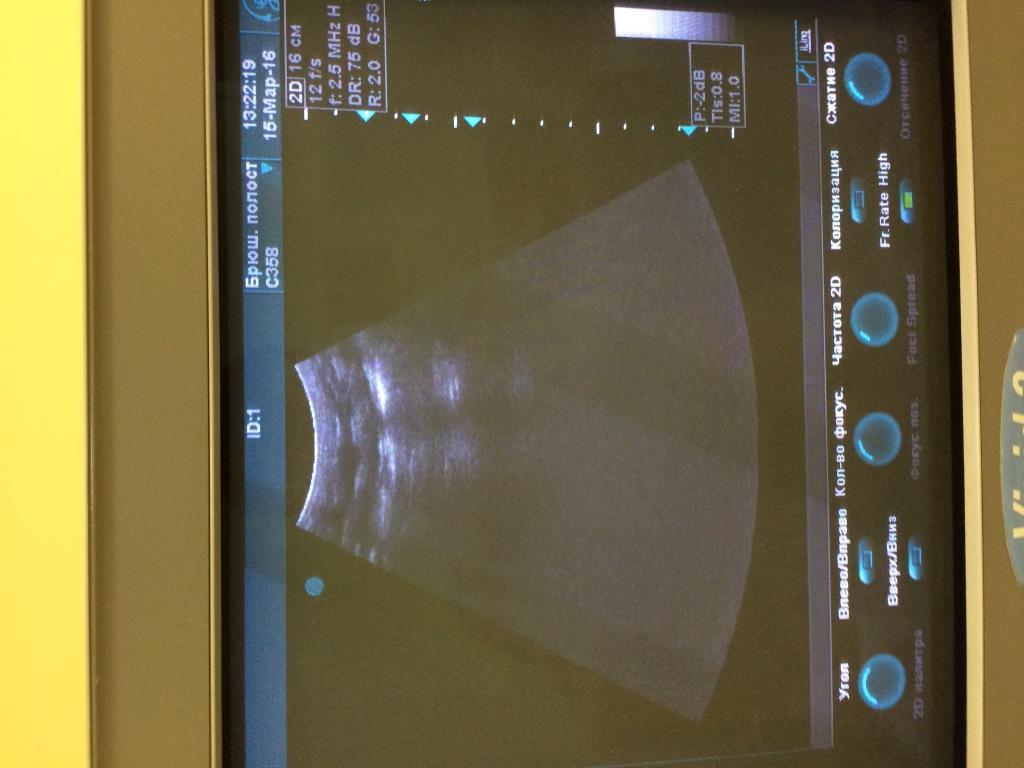

Аппарат Vivid 3 Pro корпорации General Electric Company (производственно-торговый бренд - "GE"), США, 2007 года.

При работе на конвексном и линейном датчике появляется картинка как на фото. Если убираю фокусные зоны либо понижаю частоту дефект пропадает.

Датчики вставлены в разные разъёмы. На конвексном есть небольшой порез акустической линзы, линейный без повреждений.

Предполагаю, что дело не в датчиках.